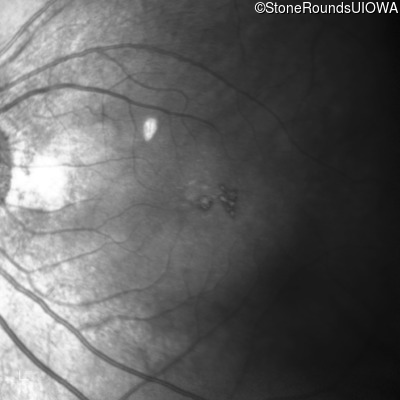

Fundus Photography - Right - 20/25

Exemplar

Fundus Photography - Left - 20/40 +1